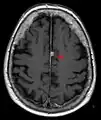

- T1-weighted (T1W) images: Cerebrospinal fluid is dark. T1-weighted images are useful for visualizing normal anatomy.

T1 (note CSF is dark) with contrast (arrow pointing to meningioma of the falx)